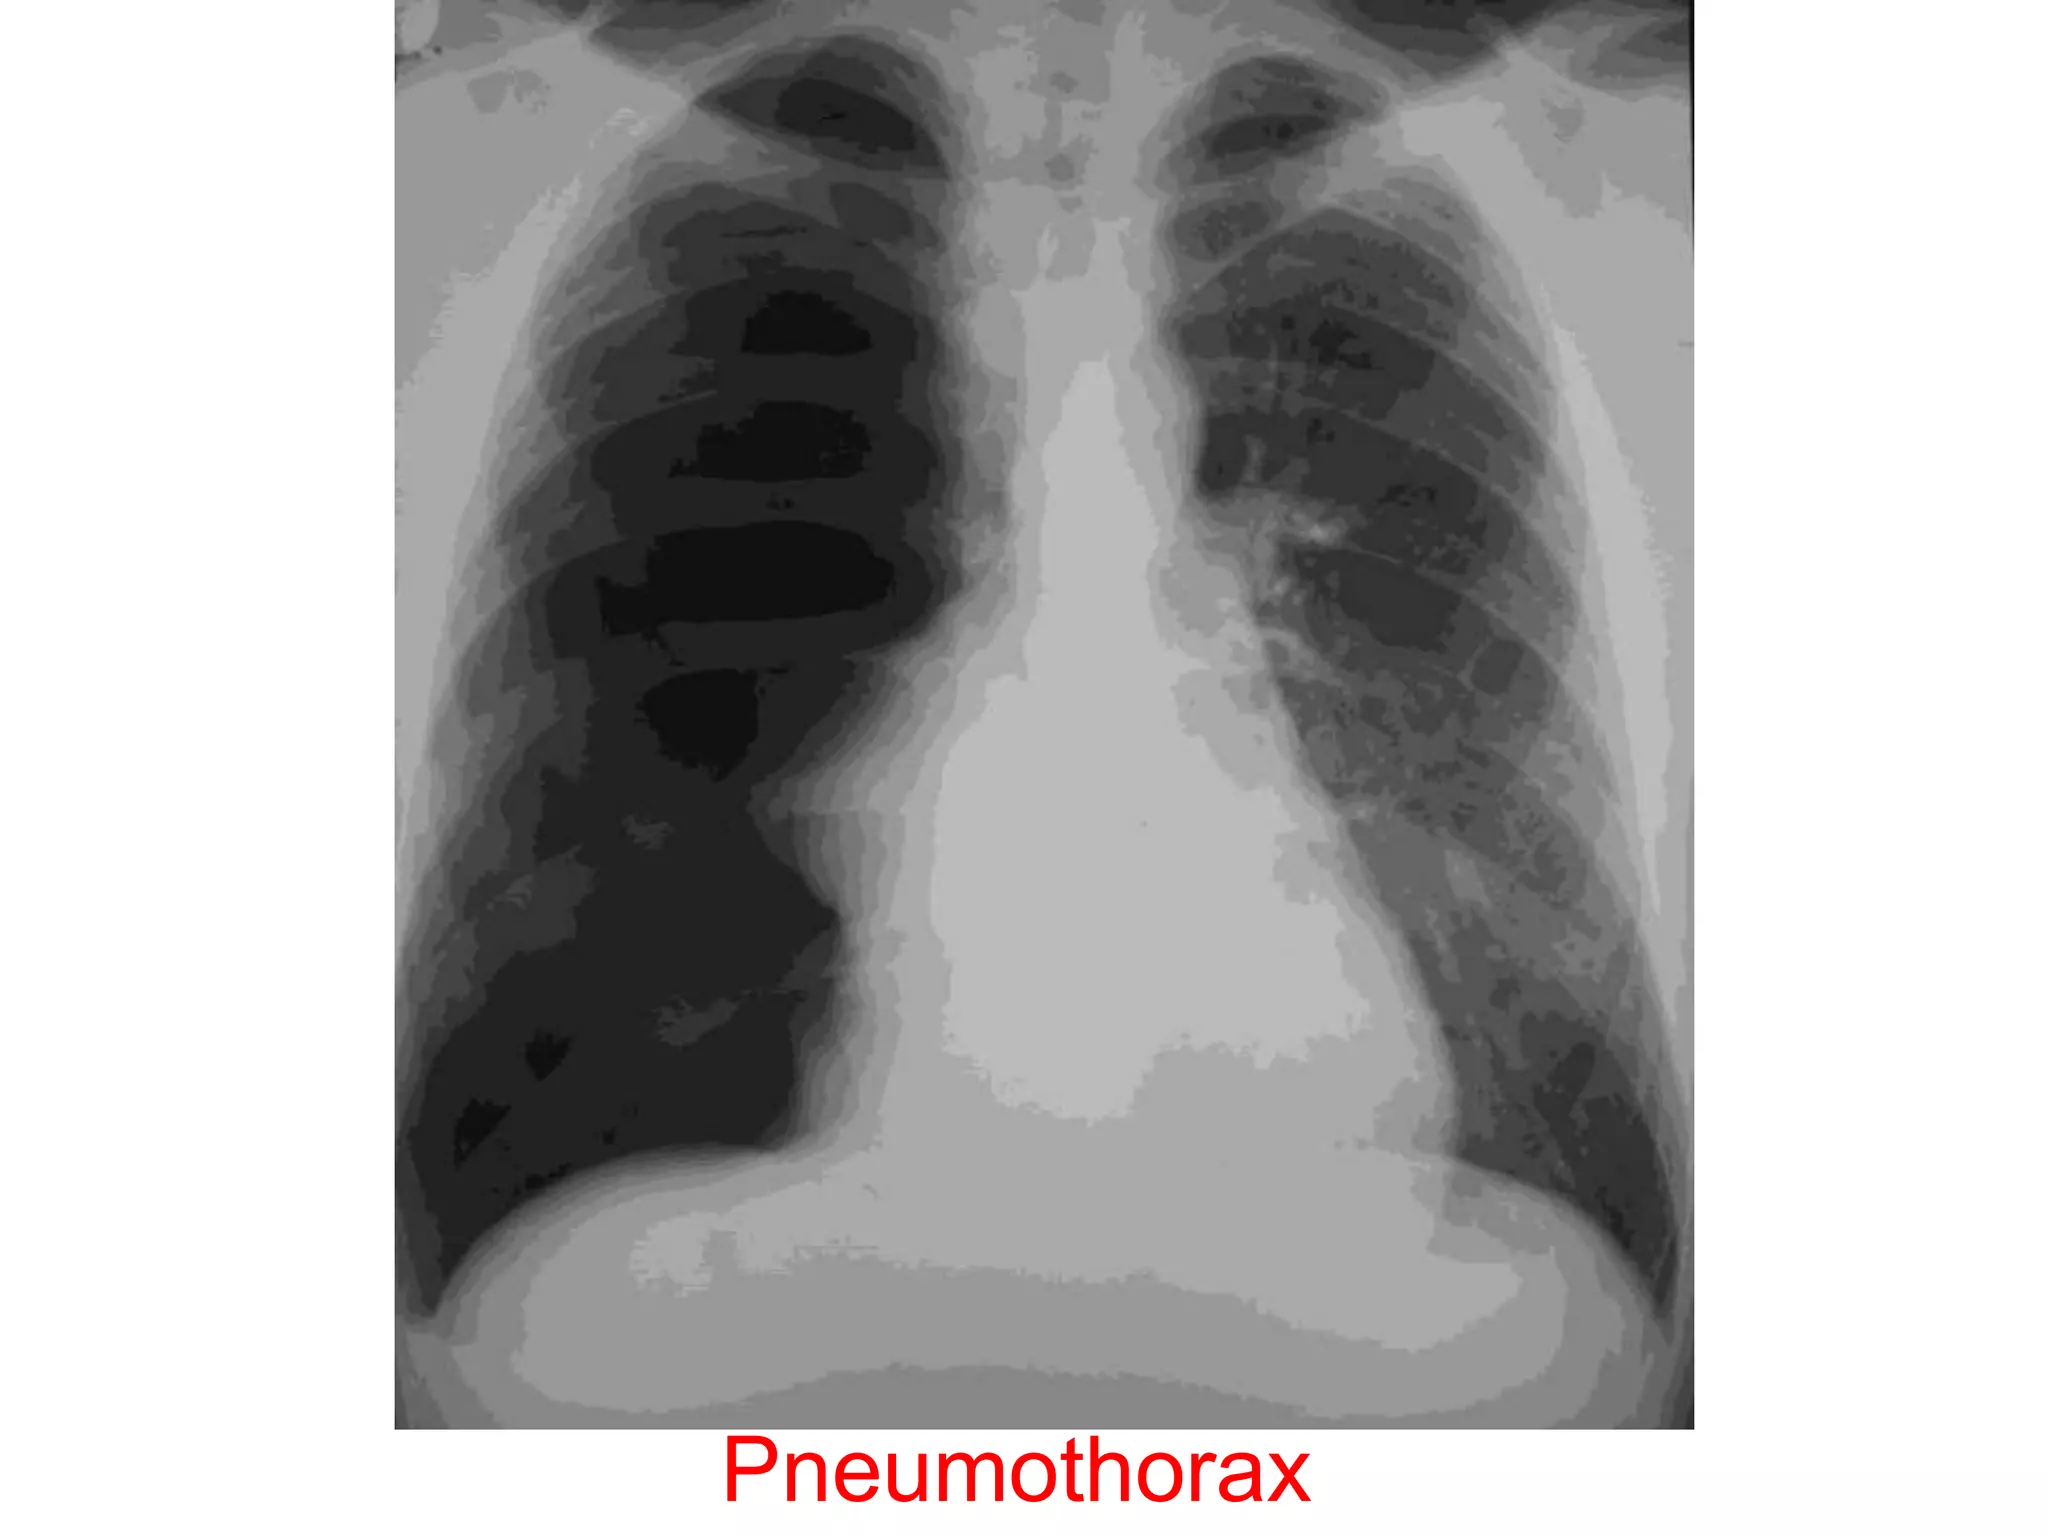

• Chest X-ray PA view showing the sharply

defined edge of the deflated lung with

complete translucency (no lung markings, no

vascular markings) between this and the chest

wall in the Rt side with shifting of

mediastinum to left.

• Suggestive of Rt Tension Pneumothorax

Pneumothorax